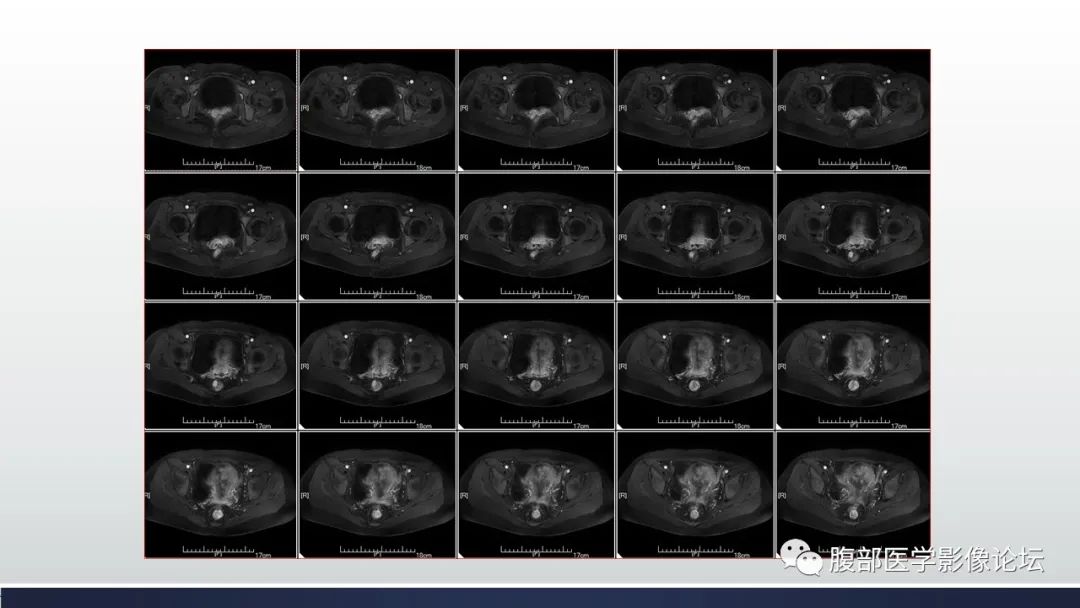

【病例】子宫内膜透明细胞癌1例MR-5

【病例】子宫内膜透明细胞癌1例MR-6

【病例】子宫内膜透明细胞癌1例MR-7

【病例】子宫内膜透明细胞癌1例MR-8